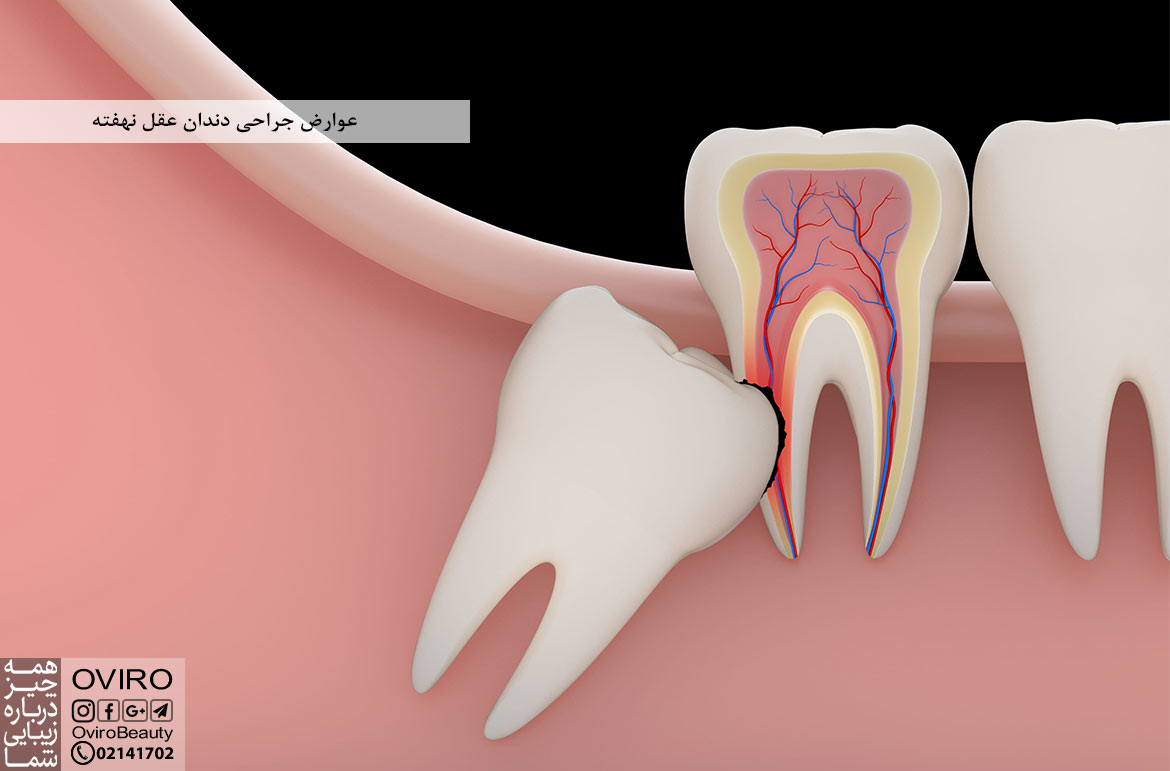

عوارض جراحی دندان عقل نهفته

نهفته بودن دندان عقل زمانی است که دندان به درستی از لثه بیرون نیامده باشد، علت – علائم – کشیدن…